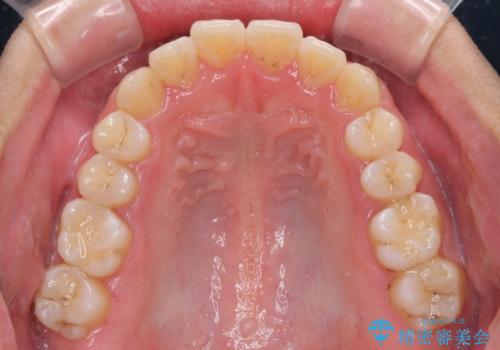

狭い歯列と前歯のデコボコ インビザラインによる矯正治療

- 上下前歯のデコボコを気にして来院された患者様です。

インビザラインによる上下歯列の拡大と、IPR(歯と歯の間を削る)にるスペースの獲得により、前歯のデコボコと狭い歯列を改善することとしました。

比較的軽度な歯列不正であったため、治療期間はそれほど長くはならないと予想されました。

また、仕上がりの歯列にも若干の叢生が残ってしまいました。